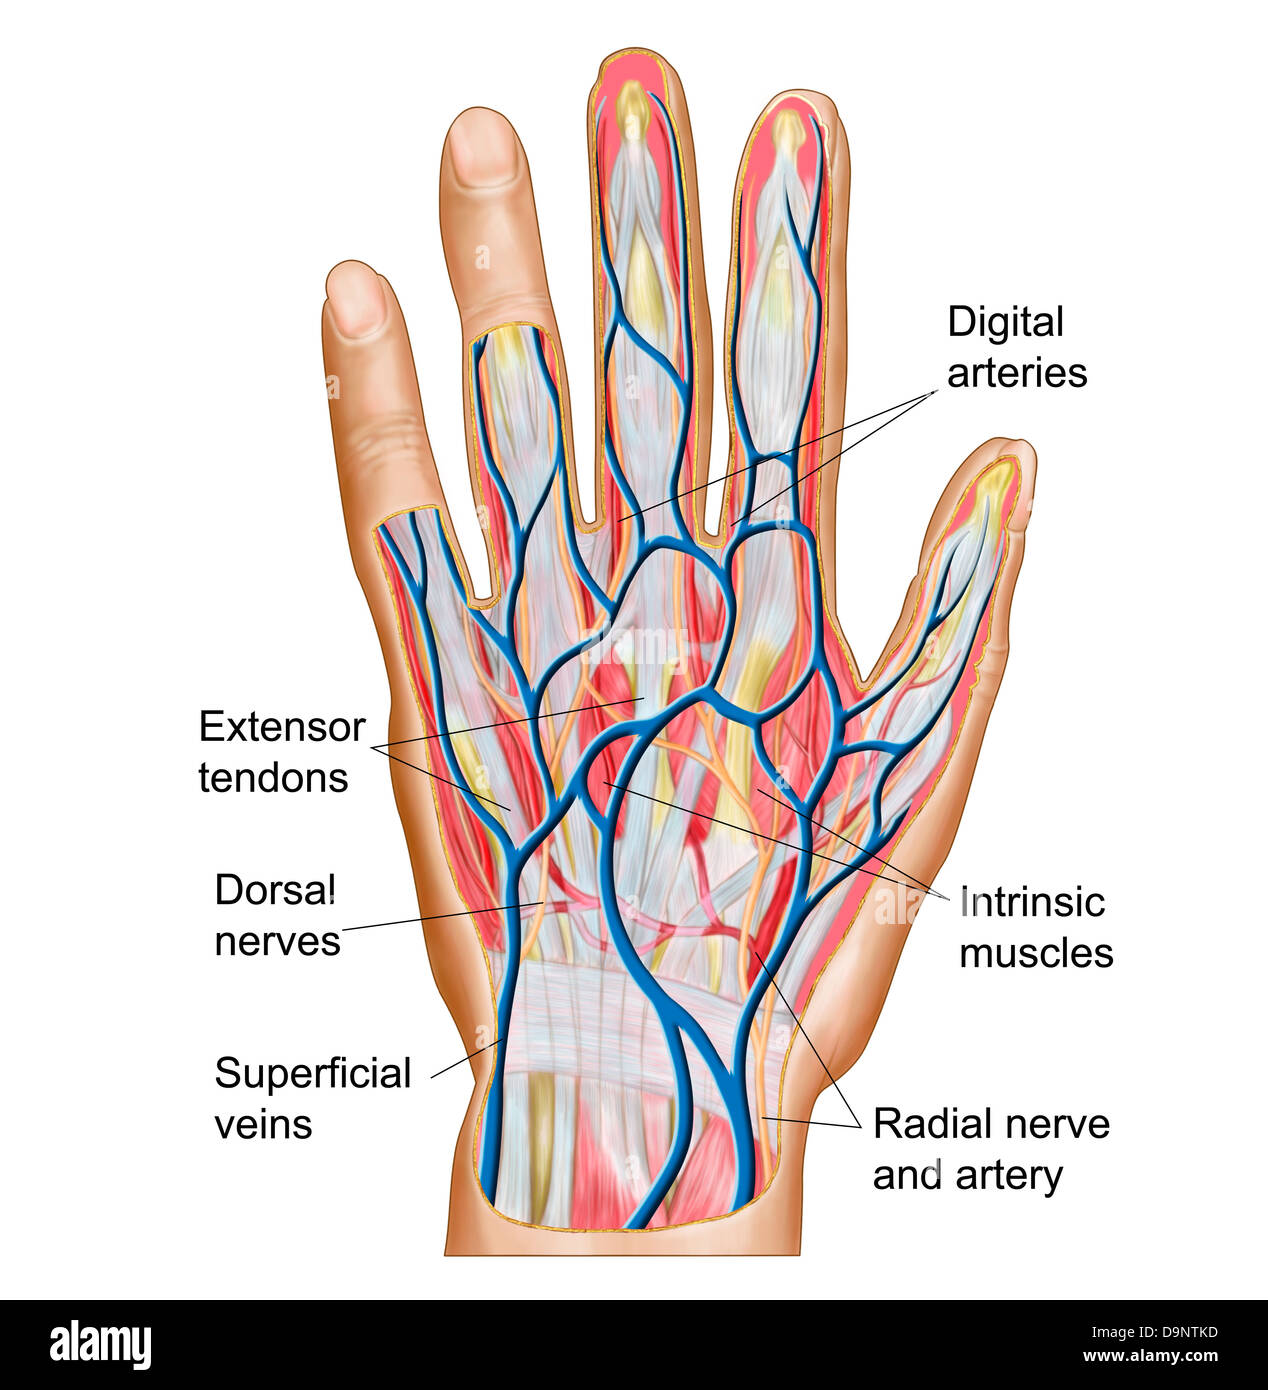

Anatomy of back of human hand. Stock Photohttps://www.alamy.com/image-license-details/?v=1https://www.alamy.com/stock-photo-anatomy-of-back-of-human-hand-57643357.html

Anatomy of back of human hand. Stock Photohttps://www.alamy.com/image-license-details/?v=1https://www.alamy.com/stock-photo-anatomy-of-back-of-human-hand-57643357.htmlRFD9NTK9–Anatomy of back of human hand.